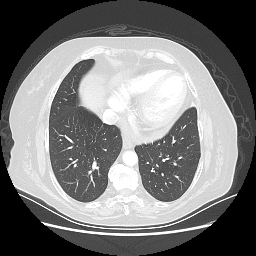

Generated VENOUS CT scan (A→B translation)

No window - Raw intensity values

Lung window (WL -600, WW 1500 β†’ Low βˆ’1350, High +150)